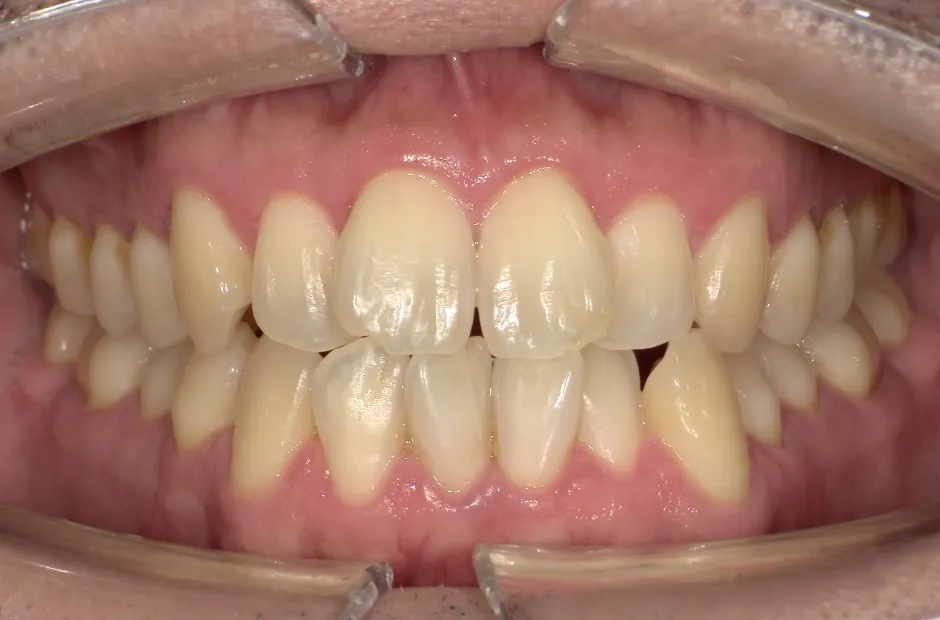

叢生

| 診断名・主訴 | 叢生 |

|---|---|

| 年齢・性別 | 43歳・女性 |

| 治療期間・回数 | 2年7か月 27回 |

| 治療に用いた主な装置 | 舌側矯正 |

| 抜歯部位 | 両顎4,4 |

| 治療費 | 100万円(税抜) |

| リスク・副作用 | 装置による違和感・疼痛・歯肉退縮・歯根吸収・虫歯のリスクなど |

治療前

治療後